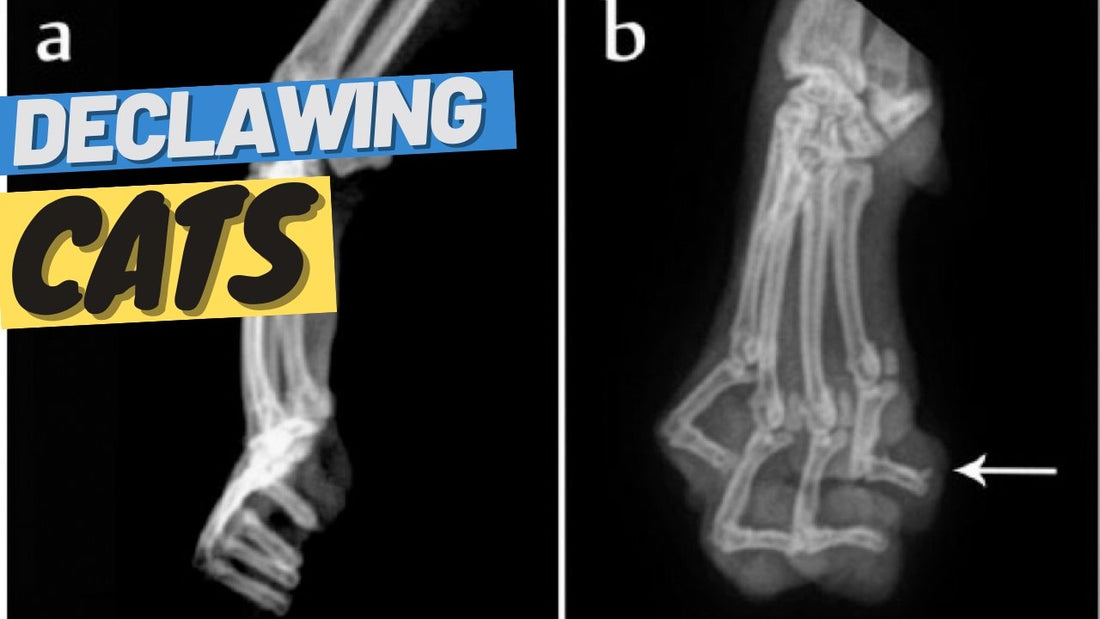

Declawing: What It Is, Why It Is Bad For Cats, and How to Avoid It - OutdoorBengal

Declawing: What It Is, Why It Is Bad For Cats, and How to Avoid It

Cat declawing (onychectomy) was first introduced in the late 1940s in the United States. It became popular in the 1950s and 1960s as more people brought cats indoors. Declawing cats... Read more...